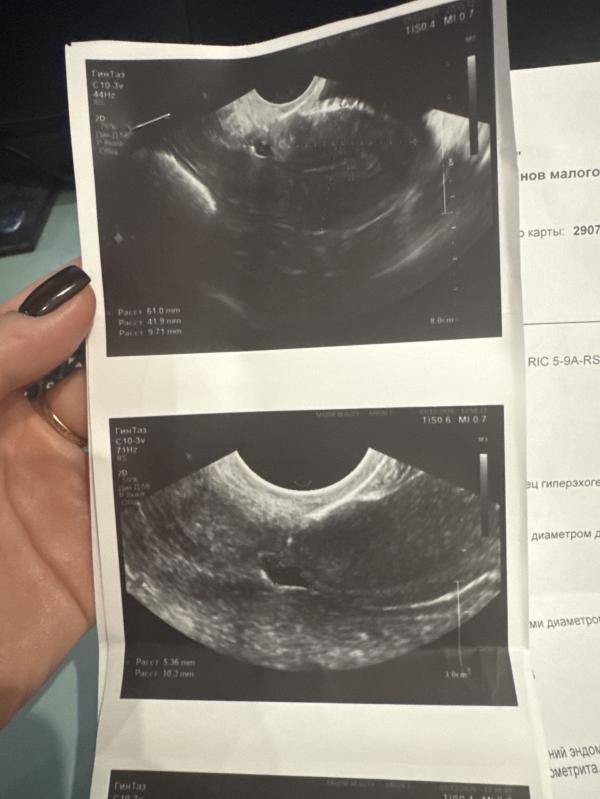

Прихожу я к ней сегодня на узи. У меня оказывается на рубце есть ниша (дырка) расслоение рубца. Что есть показание к лапороскопии. В таком состоянии нельзя беременность. Так как последствия могу быть не хорошие. И выкидыш, и разрыв матки . Нужно делать лапороскопию заново перешивать рубец. Восстановление 6-12 месяцев и уже после беременность.

И получается передняя стенка ещё очень очень маленькая. А задняя огромная

Ну и плюс ниша как дырка слева. И сам шов ещё не ровный слой